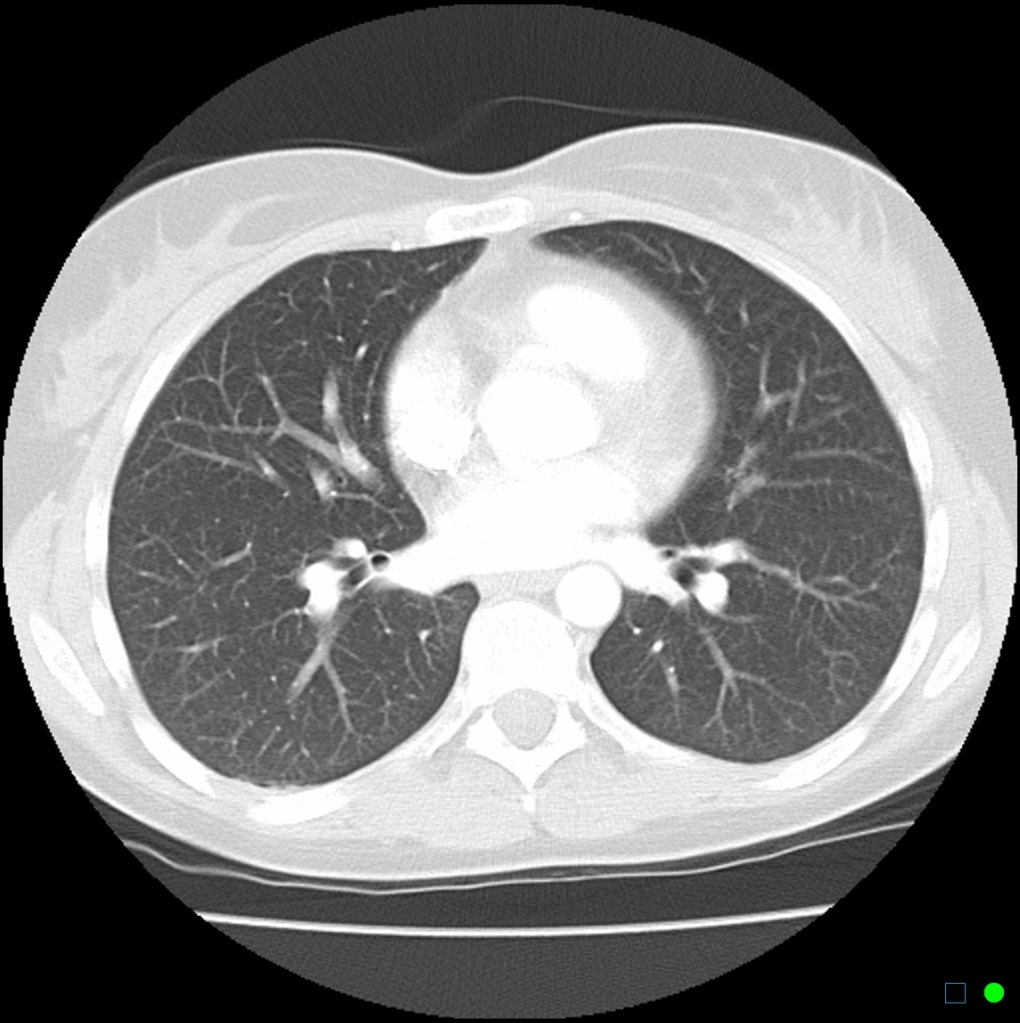

- CT scan